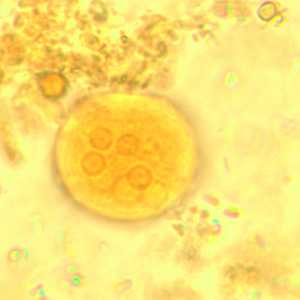

I. buetschlii cysts stained with trichrome.

Figure A: Cyst of I. buetschlii stained with trichrome. In this specimen, both the nucleus and large glycogen vacuole are visible.

Figure B: Cyst of I. buetschlii stained with trichrome. In this specimen, both the nucleus and large glycogen vacuole are visible.

Figure C: Cyst of I. buetschlii stained with trichrome. In this specimen, both the nucleus and large glycogen vacuole are visible (arrow).

Figure D: Cyst of I. buetschlii stained with trichrome. In this specimen, both the nucleus and large glycogen vacuole are visible.